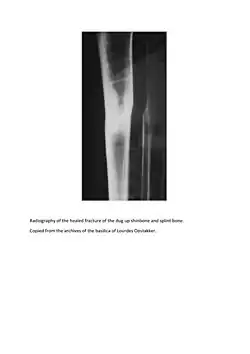

De Rudder was working for the Viscount Albéric du Bus de Gisignies when on February 16, 1867, in Jabbeke (West Flanders), a falling tree broke the two bones (tibia and fibula) of his left leg.[3]